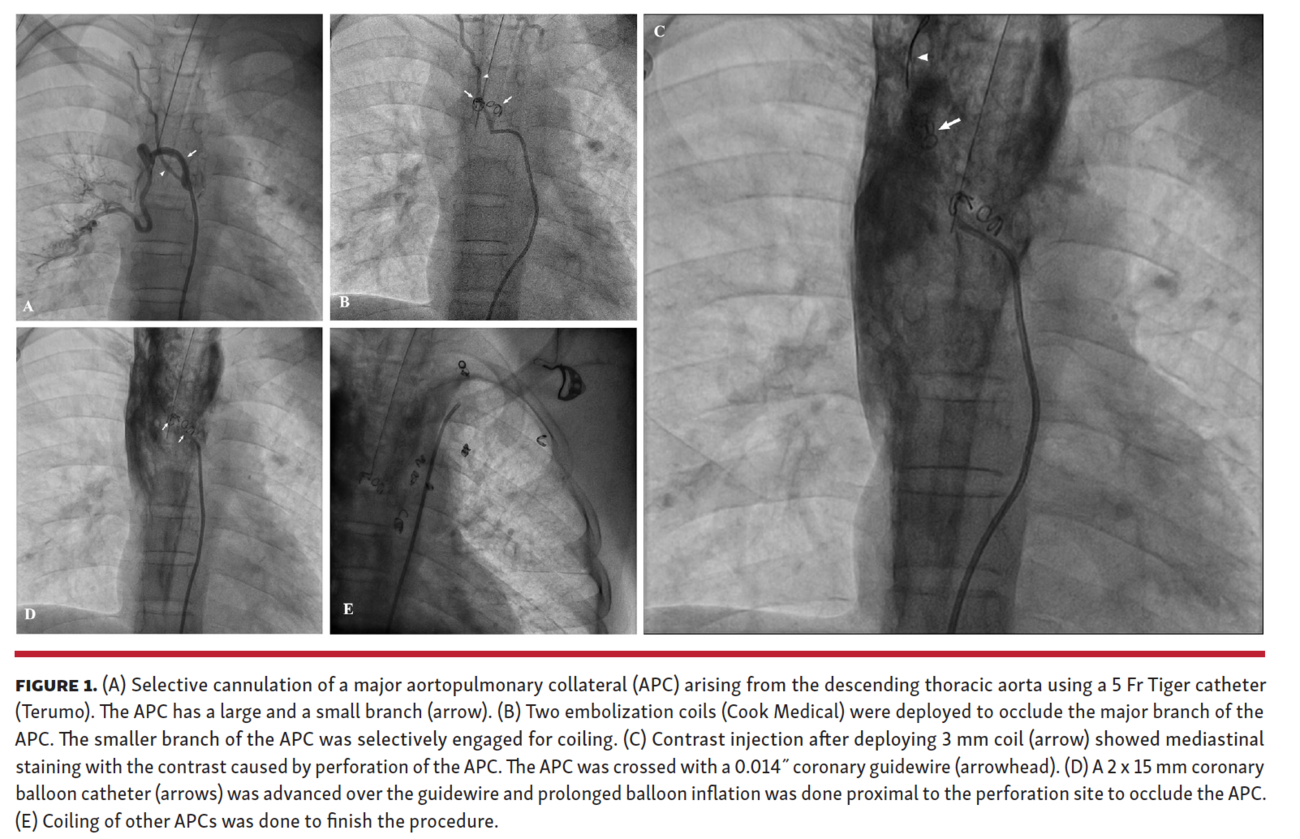

A 12-year-old boy with complex cyanotic congenital heart disease with single-ventricle physiology presented to our clinic. The patient was planned for univentricular repair. The preoperative catheterization study showed multiple large aortopulmonary collaterals (APCs) arising from the descending thoracic aorta (DTA) and the left subclavian artery. APC occlusion using thrombotic embolization coils was planned (Figure 1A). During the procedure, there was a perforation of an APC arising from the DTA (Figure 1B), resulting in extensive mediastinal contrast staining (Figure 1C). The perforation occurred because a 3 mm coil was used in an APC that was smaller than 2 mm. As the APC originated from the DTA, the perforation led to contrast staining along the planes of the mediastinum. Although no active contrast spurt was observed, repeated injections to check the status of the leak resulted in a significant staining, causing a large shadow on fluoroscopy.

We attempted to seal the perforation by prolonged balloon inflation using a 2 x 15 mm monorail coronary balloon advanced over a coronary guidewire (Figure 1D; Video 1). Protamine was given to partially reverse the anticoagulation. The leak was successfully controlled, and coiling of the remaining APCs was done (Figure 1E; Video 1). The patient underwent successful bidirectional Glenn procedure, no mediastinal collection was noted intraoperatively, and the postoperative course was uneventful.